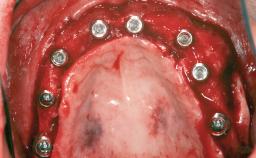

Guided Bone Regeneration (GBR) with a Particulated Autologous Graft and a ePTFE-Reinforced Membrane for Vertical Augmentation of a Single-Tooth Edentulous Space in the Esthetic Zone

# of Implants 1

Type of Implants Two-Piece

Bone Augmentation Staged|Vertical